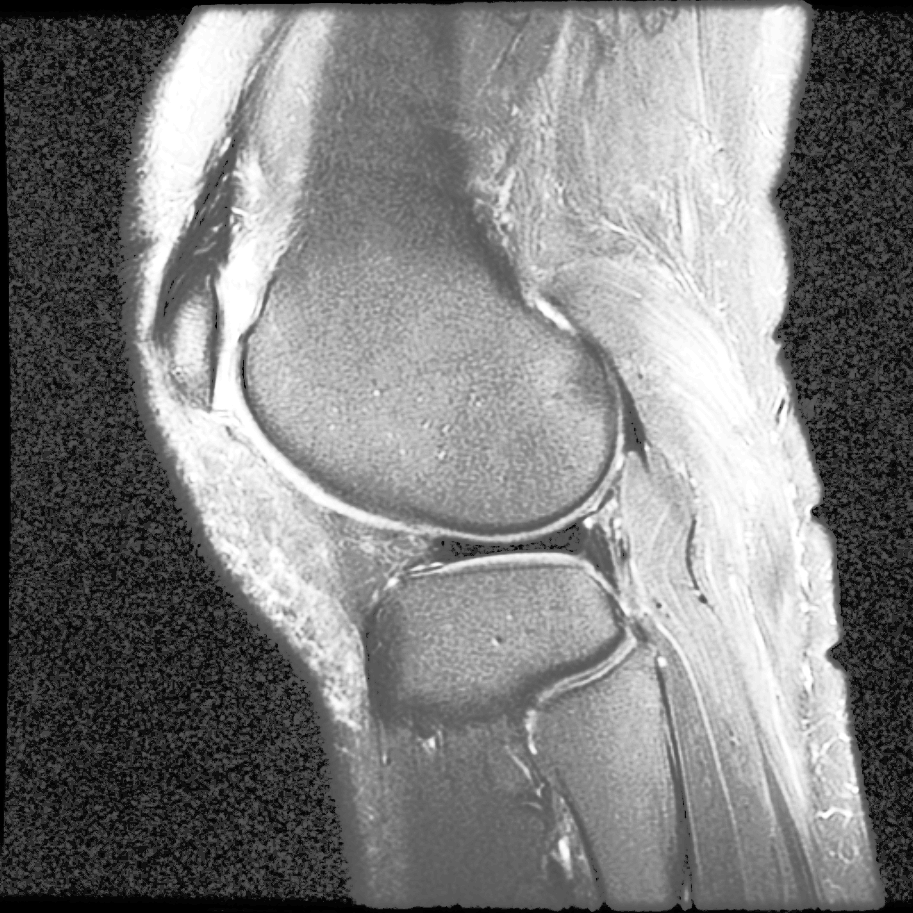

以上是直方图均衡Histogram Equalization的简单应用。事实上,HE最初用在医疗图像上。以下图为例:

如果只应用简单的HE,结果如图:

尽管组织“点亮”了,但底噪一样被“点亮”了。

MATLAB内置了adapthisteq函数,可以实现CLAHE算法。我们以Human Knee为例,看看CLAHE效果:

不仅目标被点亮了,而且低噪也被抑制了!